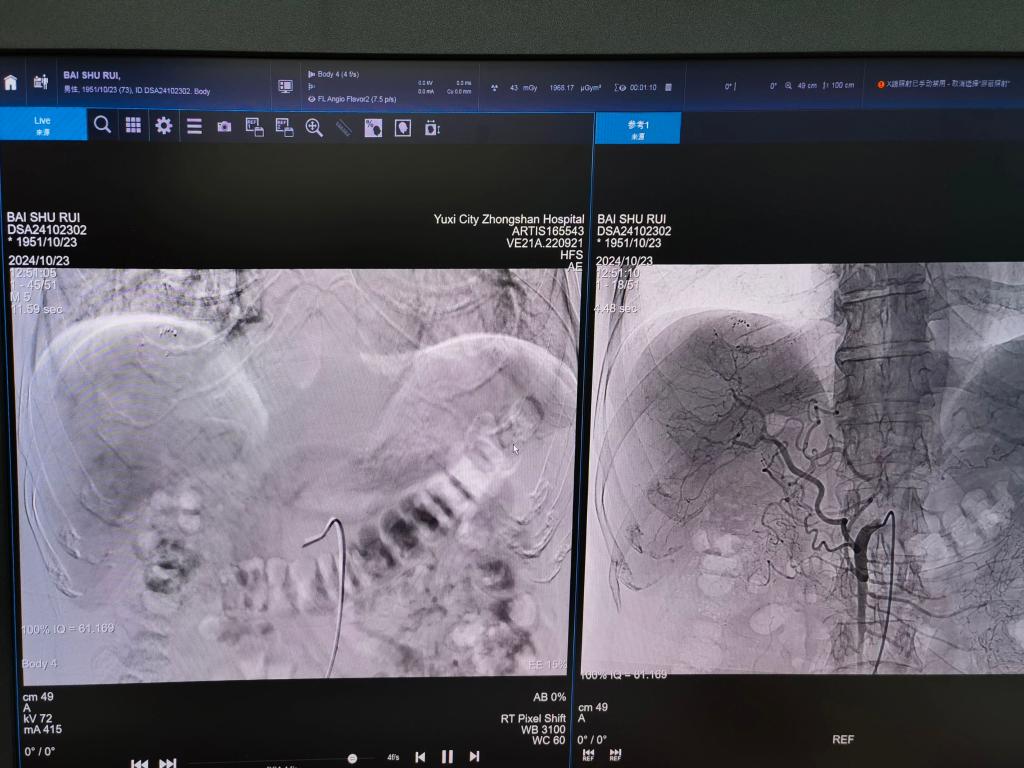

20241023日,玉溪市中山医院成功为两位中晚期肝癌患者实施了肝癌血管(C-TACE)微创介入手术。这是澄江市首次开展该项技术,标志着医院在肝癌治疗领域迈出了重要一步。

患者白大爷,有3年肝脏恶性肿瘤病史,入院后经过腹部增强CT检查后明确诊断为肝癌伴肝内转移;另一位患者陈大叔,入院后发现肝右叶出现巨大肿块,且这个巨块达15.8cm*8.9cm,有两个拳头大小,确诊为巨块型肝癌。

根据病情实际,两位患者均被诊断为中晚期肝恶性肿瘤(CNLC IIIa期)。中山大学附属第一医院肿瘤介入科范文哲教授和玉溪市中山医院肿瘤诊疗中心主任王四明,带领肿瘤诊疗中心团队对两例病例进行了全面分析和讨论。考虑到肿瘤进展迅速、患者生存期较短,决定采用精准治疗肿瘤的先进技术——肝癌血管(C-TACE)微创介入手术来为患者进行治疗。这项技术创伤小、出血少、恢复快,对于中晚期肝癌患者来说,能够有效地控制肿瘤生长,延长生存期。

在范文哲教授的指导下,由王四明带领肿瘤诊疗中心团队在介入手术室成功开展了C-TACE微创介入手术。手术过程中,医护人员紧密配合,通过介入手段穿刺股动脉,成功置入导管将化疗药物直接送至肿瘤病灶内。手术过程顺利,目前两位患者病情稳定,处于恢复阶段,并对此次手术治疗效果表示肯定。